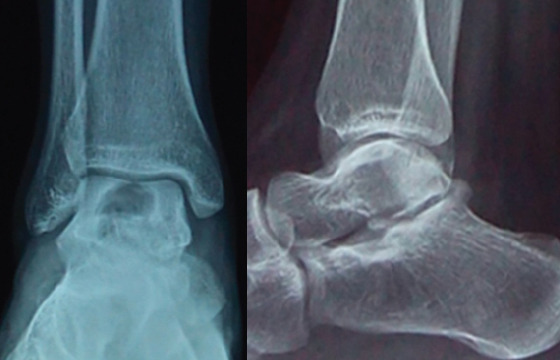

Case report: We report a case of this rare lesion managed in our department. It was a 16-year-old girl who presented with heel pain at walk, without any trauma. Radiologic explorations found a pathologic fracture of the right talus due to a bone cyst. A surgical procedure was proceeded, with curettage, and bone grafting completed by a plastered immobilization. Histopathology confirmed the diagnosis of ABC. Consolidation was achieved in 2 months, and there was no recurrence after 5 years.